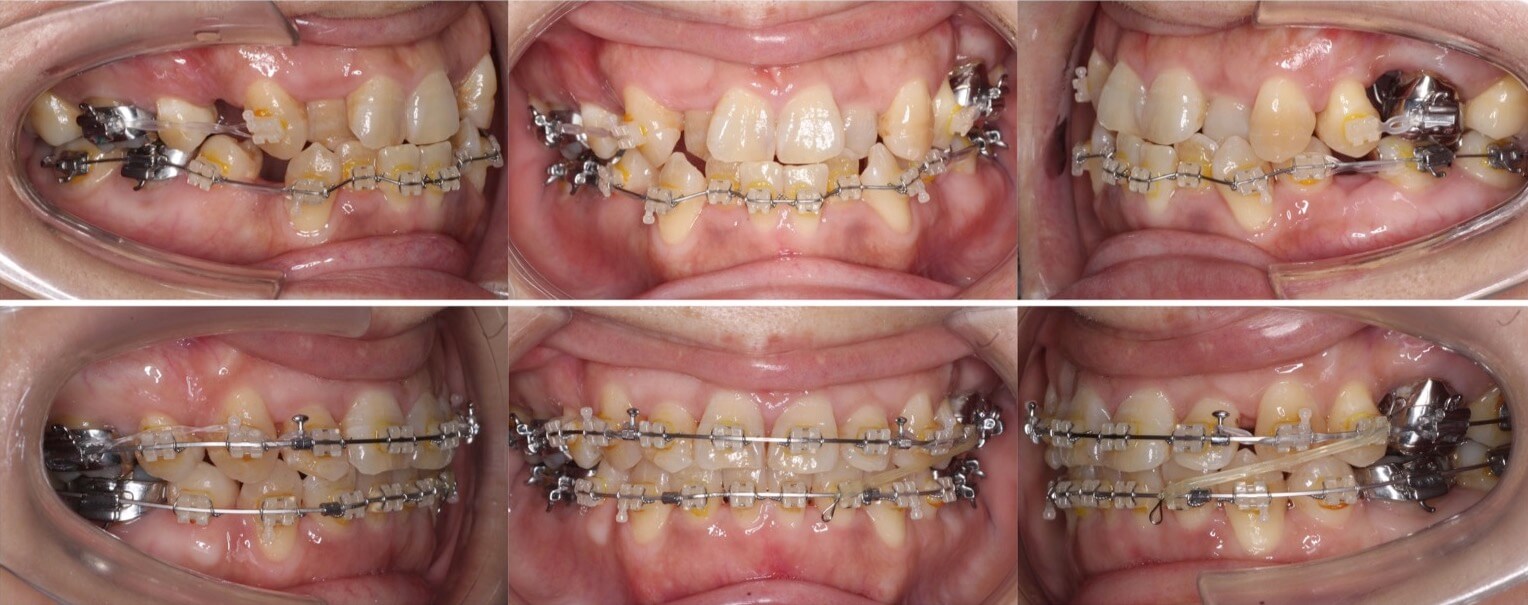

43歳女性・唇側矯正装置・抜歯

<症例概要>

主訴:前歯のがたつきと・かみ合わせ

年齢・性別:43歳女性

住まい:千葉県佐倉い市

症状:叢生・前歯交叉咬合・左上5番萌出不全

治療方針:右上下4番・左上下5番(計4本)

治療装置:唇側矯正装置

固定装置:リンガルアーチ

治療期間:2年6か月

リテーナー:下フィックス+上下クリアタイプ

治療費用:968,000(税込)

代表的副作用:痛み・治療後の後戻り・歯根吸収・歯髄壊死・歯肉退縮

▶︎その他の副作用

抜歯矯正ではふつう4番を抜歯するのですが、歯の状況によっては5番を抜歯することもあります。左上の5番の歯が半分弱しか出てきてないことと、左下の5番が大きく外側に転位していることから、左側のみ5番を抜歯し矯正治療を行いました。やや歯列の正中線は、4番を抜歯した右側に引っ張られたのですが、患者さんはそこまで気にしていませんでした。